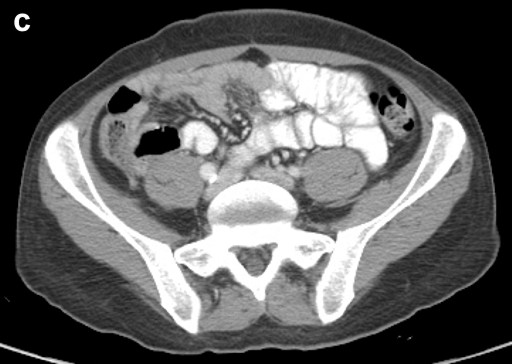

Thus, EUS-guided transduodenal biliary drainage (EUSBD) was performed. A linear array echoendoscope (GF-UCT140, Olympus America, Center Valley, PA, USA) was placed in the duodenal bulb allowing visualization of a dilated common bile duct (Figure 1). A 19-gauge FNA needle (Wilson-Cook Endoscopy, Winston-Salem, NC, USA) was used to perform a transduodenal puncture of the common bile duct through the proximal end of the duodenal stent. Bile was aspirated and a cholangiogram demonstrated good filling of the right and left duct systems with no evidence of a stricture proximal to the puncture site (Figure 2). Under fluoroscopy, a 0.035-inch straight guidewire (Jagwire, Boston Scientific Corporation, Natick, MA, USA) was passed into the biliary tree and directed toward the hilum. The FNA needle was exchanged for a biliary dilating balloon (Hurricane RX, Boston Scientific Corporation, Natick, MA, USA). The choledochoduodenostomy tract was dilated to 6 mm. A 10x60 mm fully covered self-expanding metal biliary stent (Wallfex®, Boston Scientific Corporation, Natick, MA, USA) was placed over the guidewire and deployed under fluoroscopy. One cm of the stent was left protruding into the duodenal bulb through the mesh at the proximal end of the duodenal stent (Figure 3). Good bile and contrast efflux was seen. The final fluoroscopic image did not demonstrate a bile leak (Figure 4). Post-procedure CT imaging demonstrated good positioning of the biliary stent and no evidence of a bile leak (Figure 5).

Figure 5. Post-procedure CT demonstrating: a. juxtaposition of metal biliary (yellow arrow) and duodenal (green arrow) stents with no evidence of a bile leak; b. fully covered metal biliary stent (yellow arrow) terminating in the common bile duct; c. no evidence of pelvic ascites to suggest a bile leak. |